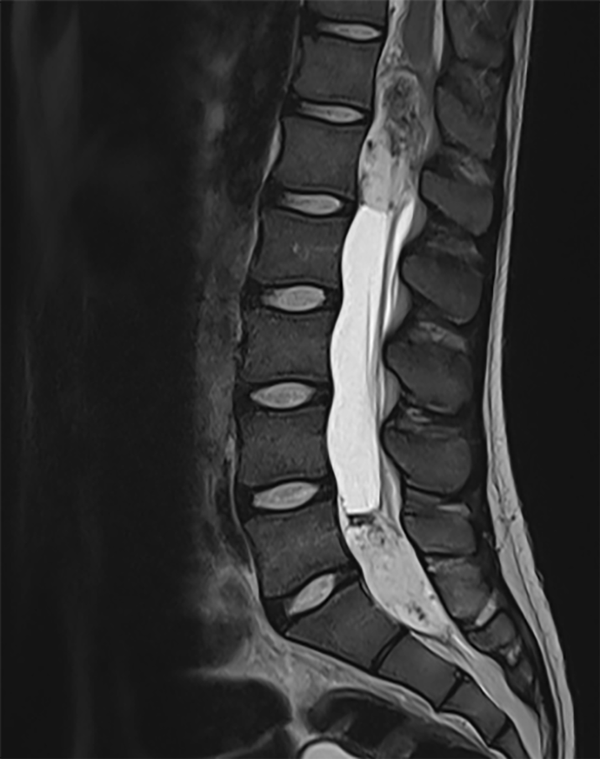

Se realizan imágenes de Resonancia Magnética (RM) de cerebro simple en donde se evidencia ligera dilatación supra e infratentorial, sin signos de paso de líquido transependimario. RM de columna total evidencia lesión nodular, expansiva, en el cono medular entre T12-L1 (18 x 20 x 53 mm) (Figura 1) que comprime las raíces de cola de caballo y el cono medular. En la region lumbosacra se evidencia una segunda imagen nodular que se localiza en la región central y distal del canal lumbar y sacro (20 x 26 x 55.5 mm) (Figura 2).

Figura 2. RMN secuencia T2: Tumor intradural intramedular L5-S1